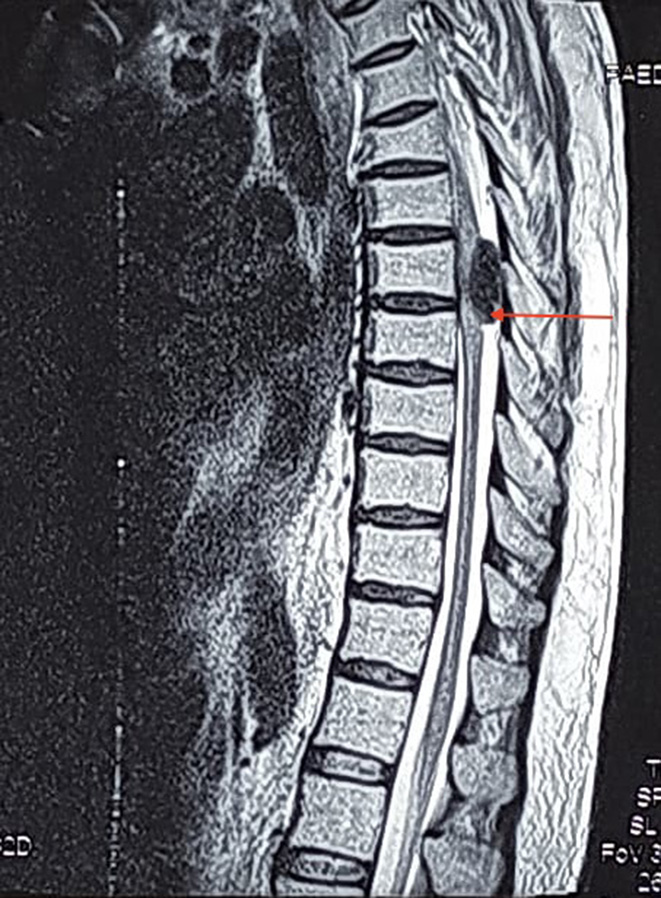

He had bladder and bowel incontinence. The remainder of his physical examination was within normal limits. Magnetic resonance imaging (MRI) of his spine revealed a T1 hyperintense and T2 hypointense lesion at the level of D4 vertebra. (Figures 1A, 1B, 2A and 2B). The lesion was homogeneously enhancing on contrast and was located intradurally and extramedullary on the left side. A differential diagnosis of metastatic lesion was made and thorough metastatic workup done, which however failed to show any primary tumour elsewhere.

Fig. 1A. Saggital T2-weighted MRI showing a hypointense lesion compressing the spinal cord at D4 level (red arrow)

Malignant melanotic nerve sheath tumour (MMNST) occurs due to melanogenesis of Schwann cells [7]. The most common syndromic association is Carney complex in 50% of cases [5]. Carney complex includes autosomal dominant disorder comprising of myxomas such as cardiac, cutaneous and mammary, spotty pigmentation and endocrine overactivity like Cushing’s syndrome and acromegaly [8]. Our case had none of the above features in preoperative clinical and radiological evaluation. Extramedullary spinal melanotic schwannomas typically present in the 30-40 years age group [9]. However, in our case the age of the patient was 54 years old. According to the literature, about 50% of MMNST cases has local recurrence or distant metastasis at the time of detection [9]. Metastatic workup of our case did not reveal any metastasis. MRI findings includes T1 hyperintensity and T2 hypointensity in a dumbell shaped tumour arising from nerve root [10, 11] which was consistent with our case. However, signal intensity may vary depending upon the concentration of melanin [12]. Patients undergoing surgery for MMNST should be subjected to rigorous follow-up. The differential diagnosis of MMNST includes leptomeningeal melanocytoma, ancient schwannoma, pigmented neurofibroma, biphasic sarcoma, neurilemmoma and melanoma [5].